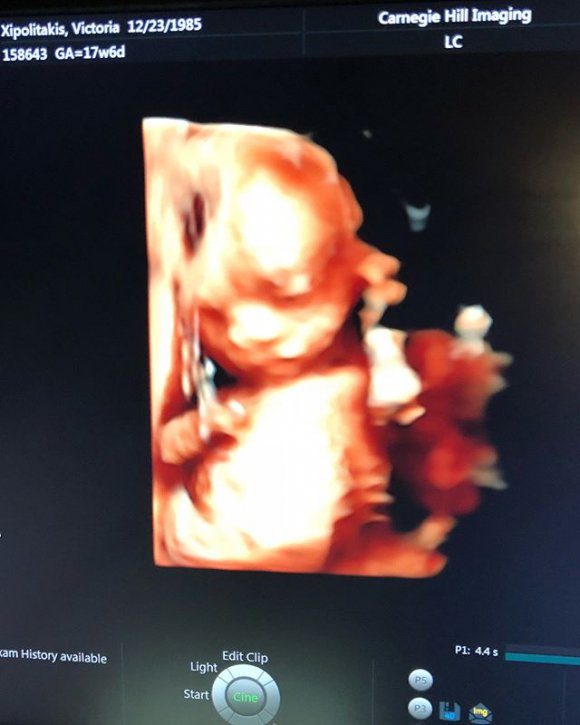

Feliz de vivir cada nueva sensación de llevar en su vientre a su primer hijo, Vicky compartió con sus seguidores varias postales de la ecografía 4D con la carita de Salvador Uriel, su bebé en camino: “Y con ustedes, les presento al milagro de cuatro meses @salvadorurielok”, escribió en Instagram.

“¡¡¡Hoy cumple 18 semanas, ya mide como un pimiento y me regalo estas imágenes. Es la primera vez que le conozco la carita y no quería dejar de compartirlo con ustedes!!!! #SeMeExplotaElCorazónDeFelicidad. ¿¿Lo ven parecido a mí???? #HijoTeAmo #SalvadorUriel”, cerró, emocionada por esta hermosa etapa de su vida.